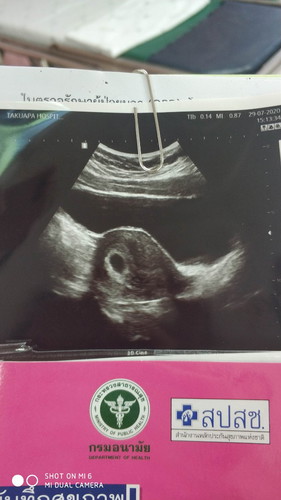

วันนี้ไป อัลตร้าซาวมา หมอไม่เห้นอะไร เจอแค่ถุงไข่แดง กลัวผิดหวังมาก เป้นเพราะเราหน้าท้องหนาด้วยไหมค่ะถึงมองเห้นยาก หรือเพราะเราอายุครรภ์ยังน้อย

บ้านนี้ซาวน์ตอน7วีคเจอแต่ถุง12วีคเจอตัวน้องค่ะ ใจเยนๆอย่าเครียดนะคะครรภ์เราอาจจะยังอ่อนยุ เดวก้เจอค่ะ